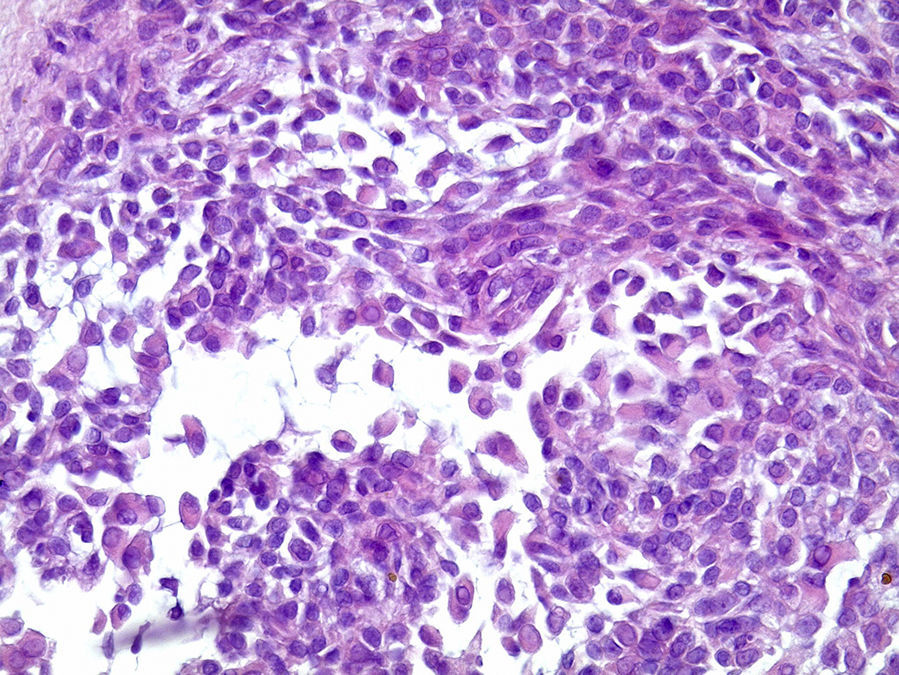

O exame histopatológico apresenta neoplasia geralmente bem delimitada por cápsula de tecido conjuntivo fibroso, com parênquima constituído por células epiteliais ductais e células mioepiteliais. Essas células frequentemente exibem diferentes morfologias gerando arquiteturas teciduais distintas dentro do mesmo tumor, motivo pelo qual foi denominado pleomórfico2,3. Podem ser encontradas áreas ductiformes, sólidas, mixoides, hialinas, plasmocitoides, osteoides e condroides, além de metaplasia escamosa6,7.

Os cortes histológicos, corados em hematoxilina e eosina, mostraram neoplasia de glândula salivar benigna, constituída por células epiteliais e mioepiteliais, parcialmente envolvida por fina cápsula de tecido conjuntivo fibroso (fig. 5). As células epiteliais encontravam‐se formando lençóis ou estruturas ductiformes, enquanto as células mioepiteliais formavam áreas mixoides, hialinas (fig. 6) ou exibiam aspecto plasmocitoide (fig. 7). O diagnóstico de adenoma pleomórfico foi confirmado. Paciente queixou‐se de desconforto no palato quando se alimentava, durante as 2 primeiras semanas após cirurgia. O paciente está sendo acompanhado clinicamente e, 2 anos após a cirurgia, não apresenta sinais de recidiva da lesão (fig. 8).

Os cortes histológicos mostraram neoplasia benigna de glândula salivar, envolvida por cápsula de tecido conjuntivo fibroso (fig. 14). O parênquima neoplásico é constituído por células epiteliais dispostas em lençóis e estruturas ductiformes, além de células mioepiteliais formando áreas mixoides e hialinas (fig. 15) ou apresentando‐se com morfologia plasmocitoide (fig. 16). O diagnóstico de adenoma pleomórfico foi confirmado. A paciente relatou ausência de dor no pós‐operatório e manteve utilização da placa de acrílico por 4 semanas. A paciente encontra‐se em acompanhamento e o exame clínico após 2 anos da remoção cirúrgica mostrou adequada cicatrização e ausência de sinais de recidiva da lesão (fig. 17).